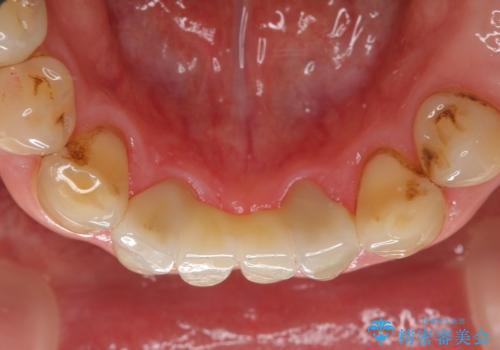

セラミックも強い衝撃で欠けないわけではないため、強度のあるフルジルコニアクラウンでブリッジを作成しました。

フルジルコニアクラウンはやや白すぎるといった難点がありますが、今回は強度を優先することにしました。

夜間の歯ぎしりによるチッピング、破折をふせぐため、ナイトガード使用をお勧めしています。